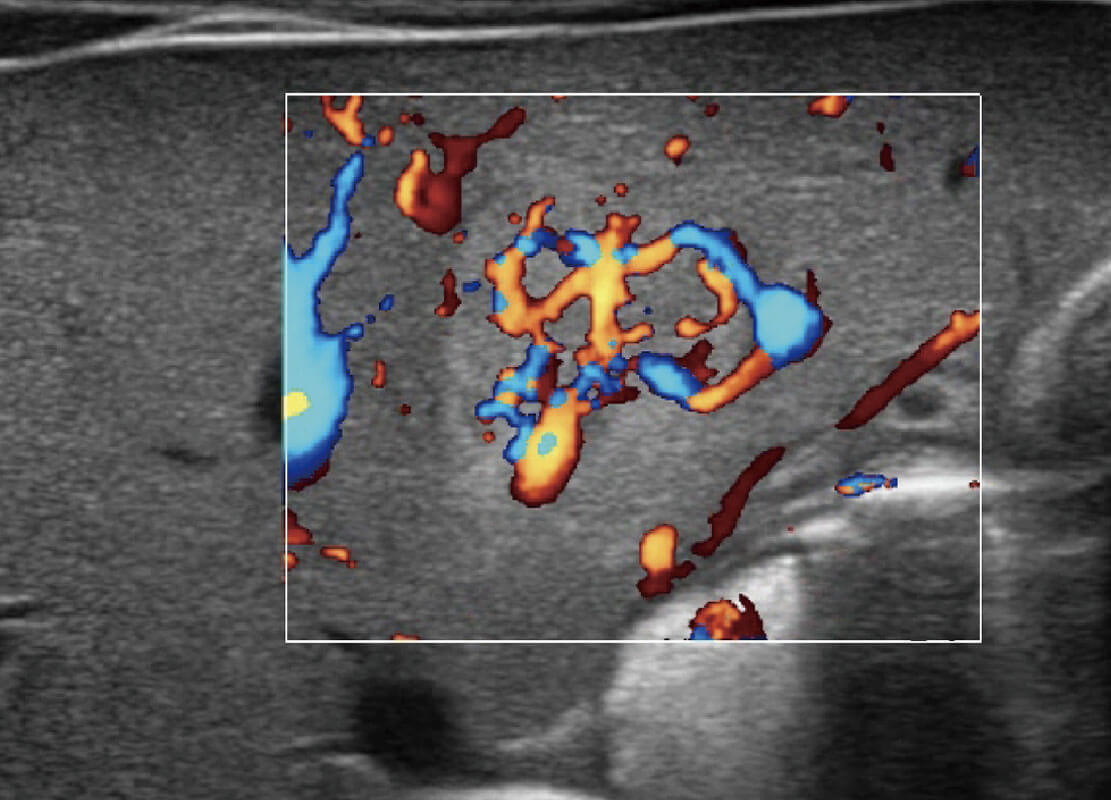

P60搭载宽频带线阵探头、宽景成像、弹性成像技术,为您提供乳腺应用方案。P60支持高频相控阵探头、线阵探头、腹部高频探头、腹部微凸探头等,丰富的探头群搭载敏感的彩色血流成像,适用于新生儿多种脏器检测要求,满足新生儿筛查需求。

乳腺导管癌

乳腺癌显微血流

新生儿肝血管癌

新生儿脊髓圆锥